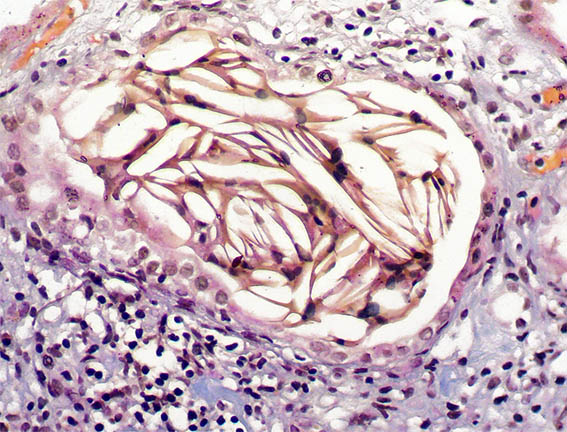

Figure 6. Methenamine-silver stain, X200.

Figure 7. H&E, X200.